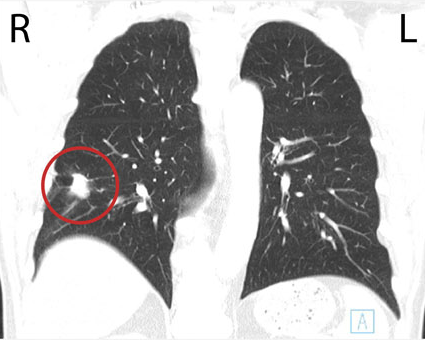

Paul's CT scan detected a 2.5 cm nodule in the lower lobe of his right lung.

A chest CT scan is similar to but much more detailed than a chest X-ray image. It allows doctors to have an accurate image of your lungs, heart, esophagus and lymph nodes.

CT stands for Computed Tomography. This painless imaging test takes many detailed X-ray images, called slices, of your lungs and the inside of your chest. Computer software combines these slices to create three-dimensional (3D) models to help show the size, shape, and position of your lungs and structures in your chest.

- The location and size of any tumour in the lung